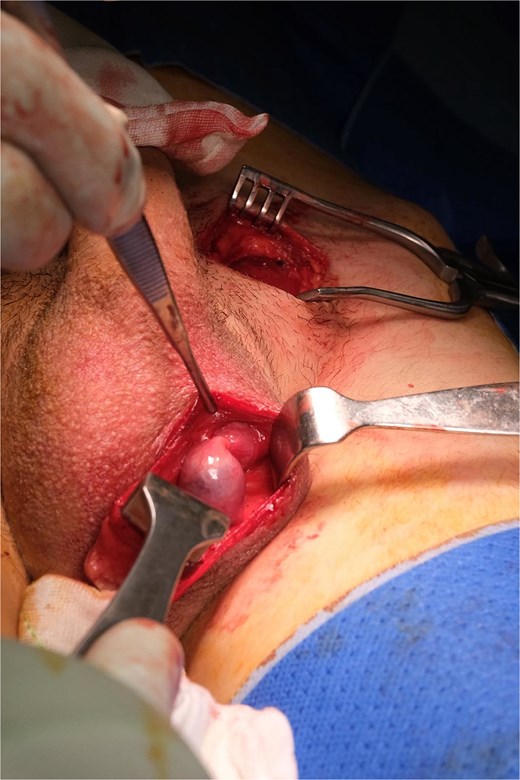

Following general anaesthetic induction, manual reduction into the scrotum was once again attempted but was unsuccessful. Exploration of the inguinal canal was planned to assess testicular viability, degree of impaction and adhesions, and the length of testicular pedicle. A left inguinal incision was made, and dissection was carried down to the inguinal canal where the left testis was found incarcerated by dense fibrotic adhesions (Fig. 3).

Intraoperative view of the left testis incarcerated within the inguinal canal and surrounded by adhesions.